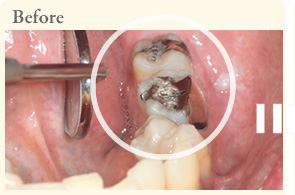

口のなかに入っている金属を取り除きます。

金属をセラミックに変更しました。